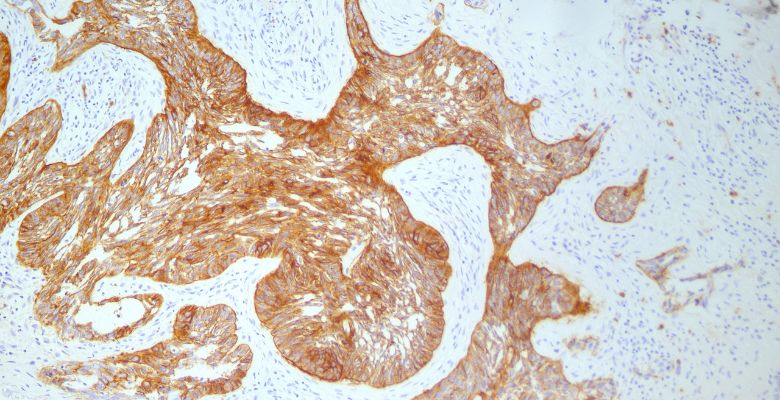

A imunohistoquímica de p53 (IHC) pode ser um método útil e atempado para a caracterização precoce das síndromes mielodisplásicas (MDS) e da leucemia mieloide aguda (LMA) com mutação TP53, de acordo com os resultados de um estudo publicado na Cancer. O tempo prolongado de resposta dos resultados de sequenciação de…